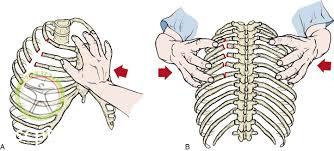

در چنین شرایطی هر دو دست را در هر طرف سینه ورزشکار آسیب دیده قرار دهید و حرکت سینه را در حین تنفس بررسی کنید اگر طی دم یک طرف سینه بالا و طرف دیگر پایین برود در سمت پایین رفته سینه حداقل سه دنده شکسته وجود دارد این وضعیت قفسه سینه شناور نامیده می شود.

در شکستگی های ساده خود فرد می تواند حرکت کند اما اگر احتمال قفسه سینه شناور وجود داشته باشد ورزشکار باید روی سمت آسیب دیده قرار بگیرد و یکپارچه لوله شده زیربخش مصدوم قرار داده این تمهیدات در را در حین تنفس کنترل میکند ورزشکار باید در این وضعیت باقی بماند تا تنفس تحت کنترل باشد اگر تنفس ورزشکار قطع شود باید ورزشکار را به پشت برگردانید تا بتواند تنفس مصنوعی بگیرد.